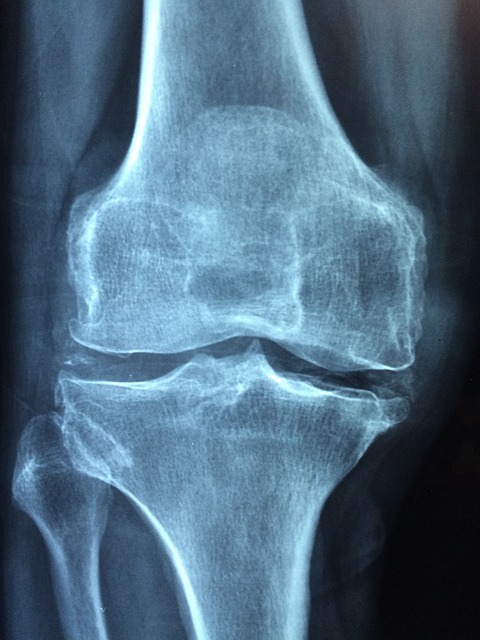

겨울철이 되면 뼈 건강 관리가 더욱 중요해집니다. 골다공증은 뼈의 밀도가 낮아져 쉽게 골절될 위험이 있는 상태를 말하는데, 겨울철에는 여러 요인으로 인해 골다공증이 악화될 수 있습니다.

겨울철에는 추운 날씨와 활동 부족으로 인해 골절 위험이 증가할 수 있습니다. 특히 골다공증 환자는 작은 충격에도 골절될 수 있기 때문에 생활 습관 개선이 필수적입니다.

비타민D는 뼈 건강에 있어 매우 중요한 영양소로, 특히 겨울철에는 부족하기 쉬운 영양소 중 하나입니다. 비타민D가 부족할 경우 체내 칼슘 흡수율이 떨어져 골다공증이 악화될 수 있으며, 뼈가 약해져 작은 충격에도 쉽게 골절될 수 있습니다.